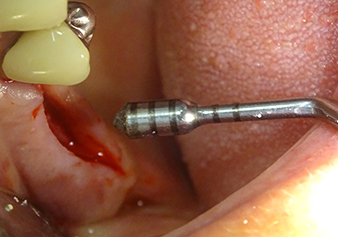

The implant bed is widened to 3.0 mm with the I3A instrument

Fig.5: In the next step, the implant bed is widened to 3.0 mm with the I3A instrument (power 100%, coolant 80%). The depth marks reliably prevent the preparation from going too deep.